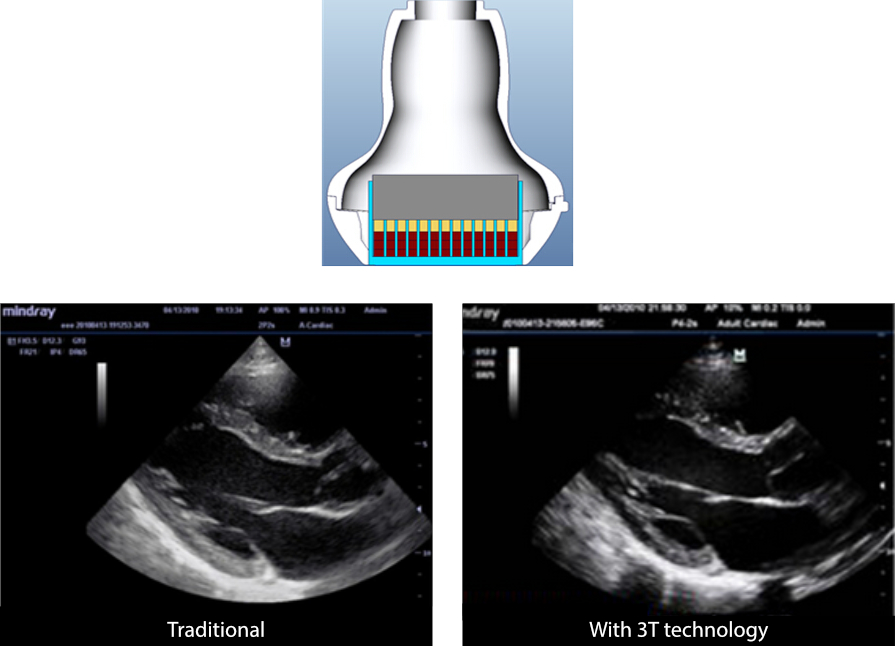

3T Transducer Technology?

Tecnologia do transdutor de patente da Mindray para aumentar a largura da banda da imagem e a eficiência da transmiss?o.

┬Ę Design com a combina??o de tr├¬s camadas para maior sensibilidade, largura de banda maior e S/N aprimorado

┬Ę Design de corte total para ru├Łdos de interfer├¬ncias menores, melhor diretividade e resolu??o lateral aprimorada

┬Ę Design de controle t├®rmico para melhor transmiss?o ac├║stica